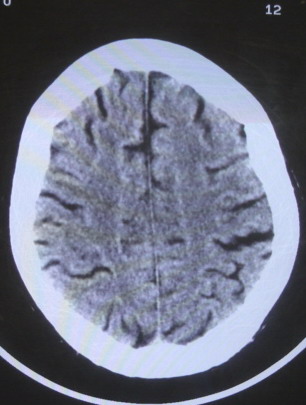

女  67岁 双下肢无力,行动不灵便

老年脑

脑萎缩,腔隙性脑梗塞.

双侧额桥束及左侧脑室旁多发腔梗塞+老年性脑改变

多发腔梗、老年性脑改变、脑白质异常。